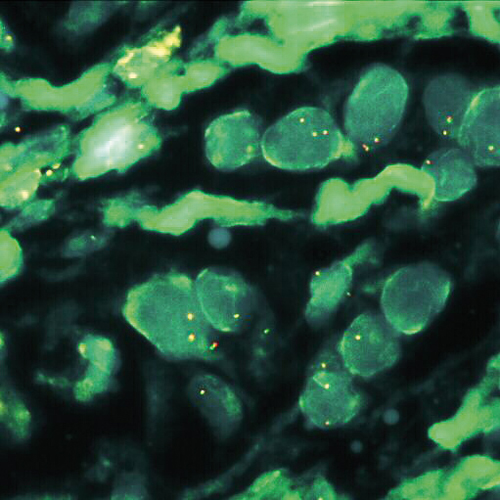

MALT1 (18q21) Break tissue probe hybridized to paraffin embedded material (2RG).

Low grade malignant lymphomas arising from mucosa associated lymphoid tissue (MALT) represent a distinct clinicopathological entity. The three major translocations seen in MALT lymphomas are t(11;18)(q21;q21) / API2-MALT1, t(14;18)(q32;q21) / IGH-MALT1 and t(1;14)(p22;q32) / IGH-BCL10. A break or split probe for MALT1 (18q21) is best used to analyze translocation of the MALT1 gene on formalin fixed paraffin embedded tissue for routine clinical diagnosis. The MALT1 (18q21) Break probe is optimized to detect translocations involving the MALT1 gene region at 18q21 in a dual-color, split assay. Kreatech has developed this probe for the specific use on cell material (KI-10608), or for the use on tissue (KI-10731).